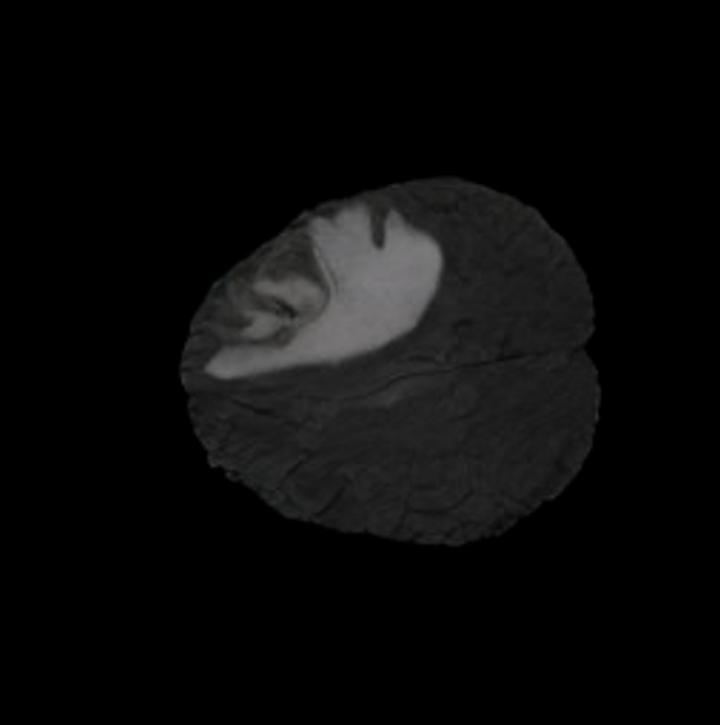

One way to test the generalization capability of the trained X-Diffusion is to test it on a completely different domain from an MRI dataset not seen during training. We report the single-slice results on the test set of knees from NYU fastMRI [33, 80], using the X-Diffusion trained on the BRATS brain MRIs. The test PSNR result is 34.17 and an example is shown in Figure 8. It shows how successfully X-Diffusion can generate knee MRIs (out-of-domain) despite being trained on brains.

The Effect of Pretraining. We hypothesize that the massive pretraining of our X-Diffusion based on Stable Diffusion weights [55] played an important role. Another aspect is that the Zero-123 [39] weights which are modified Stable Diffusion weights that understand viewpoints and fine-tuned on large 3D CAD dataset Objaverse [21] can indeed be the reason why X-Diffusion generalizes well. The PSNR for 1-slice on BRATS dataset are (SD-pretraining): 21.52 dB, (Zero-123-pretraining): 23.13 dB, (no-pretraining): 17.14 dB. These results highlight the importance of pertaining to X-Diffusion. Refer to Figure 8 for similar observation.